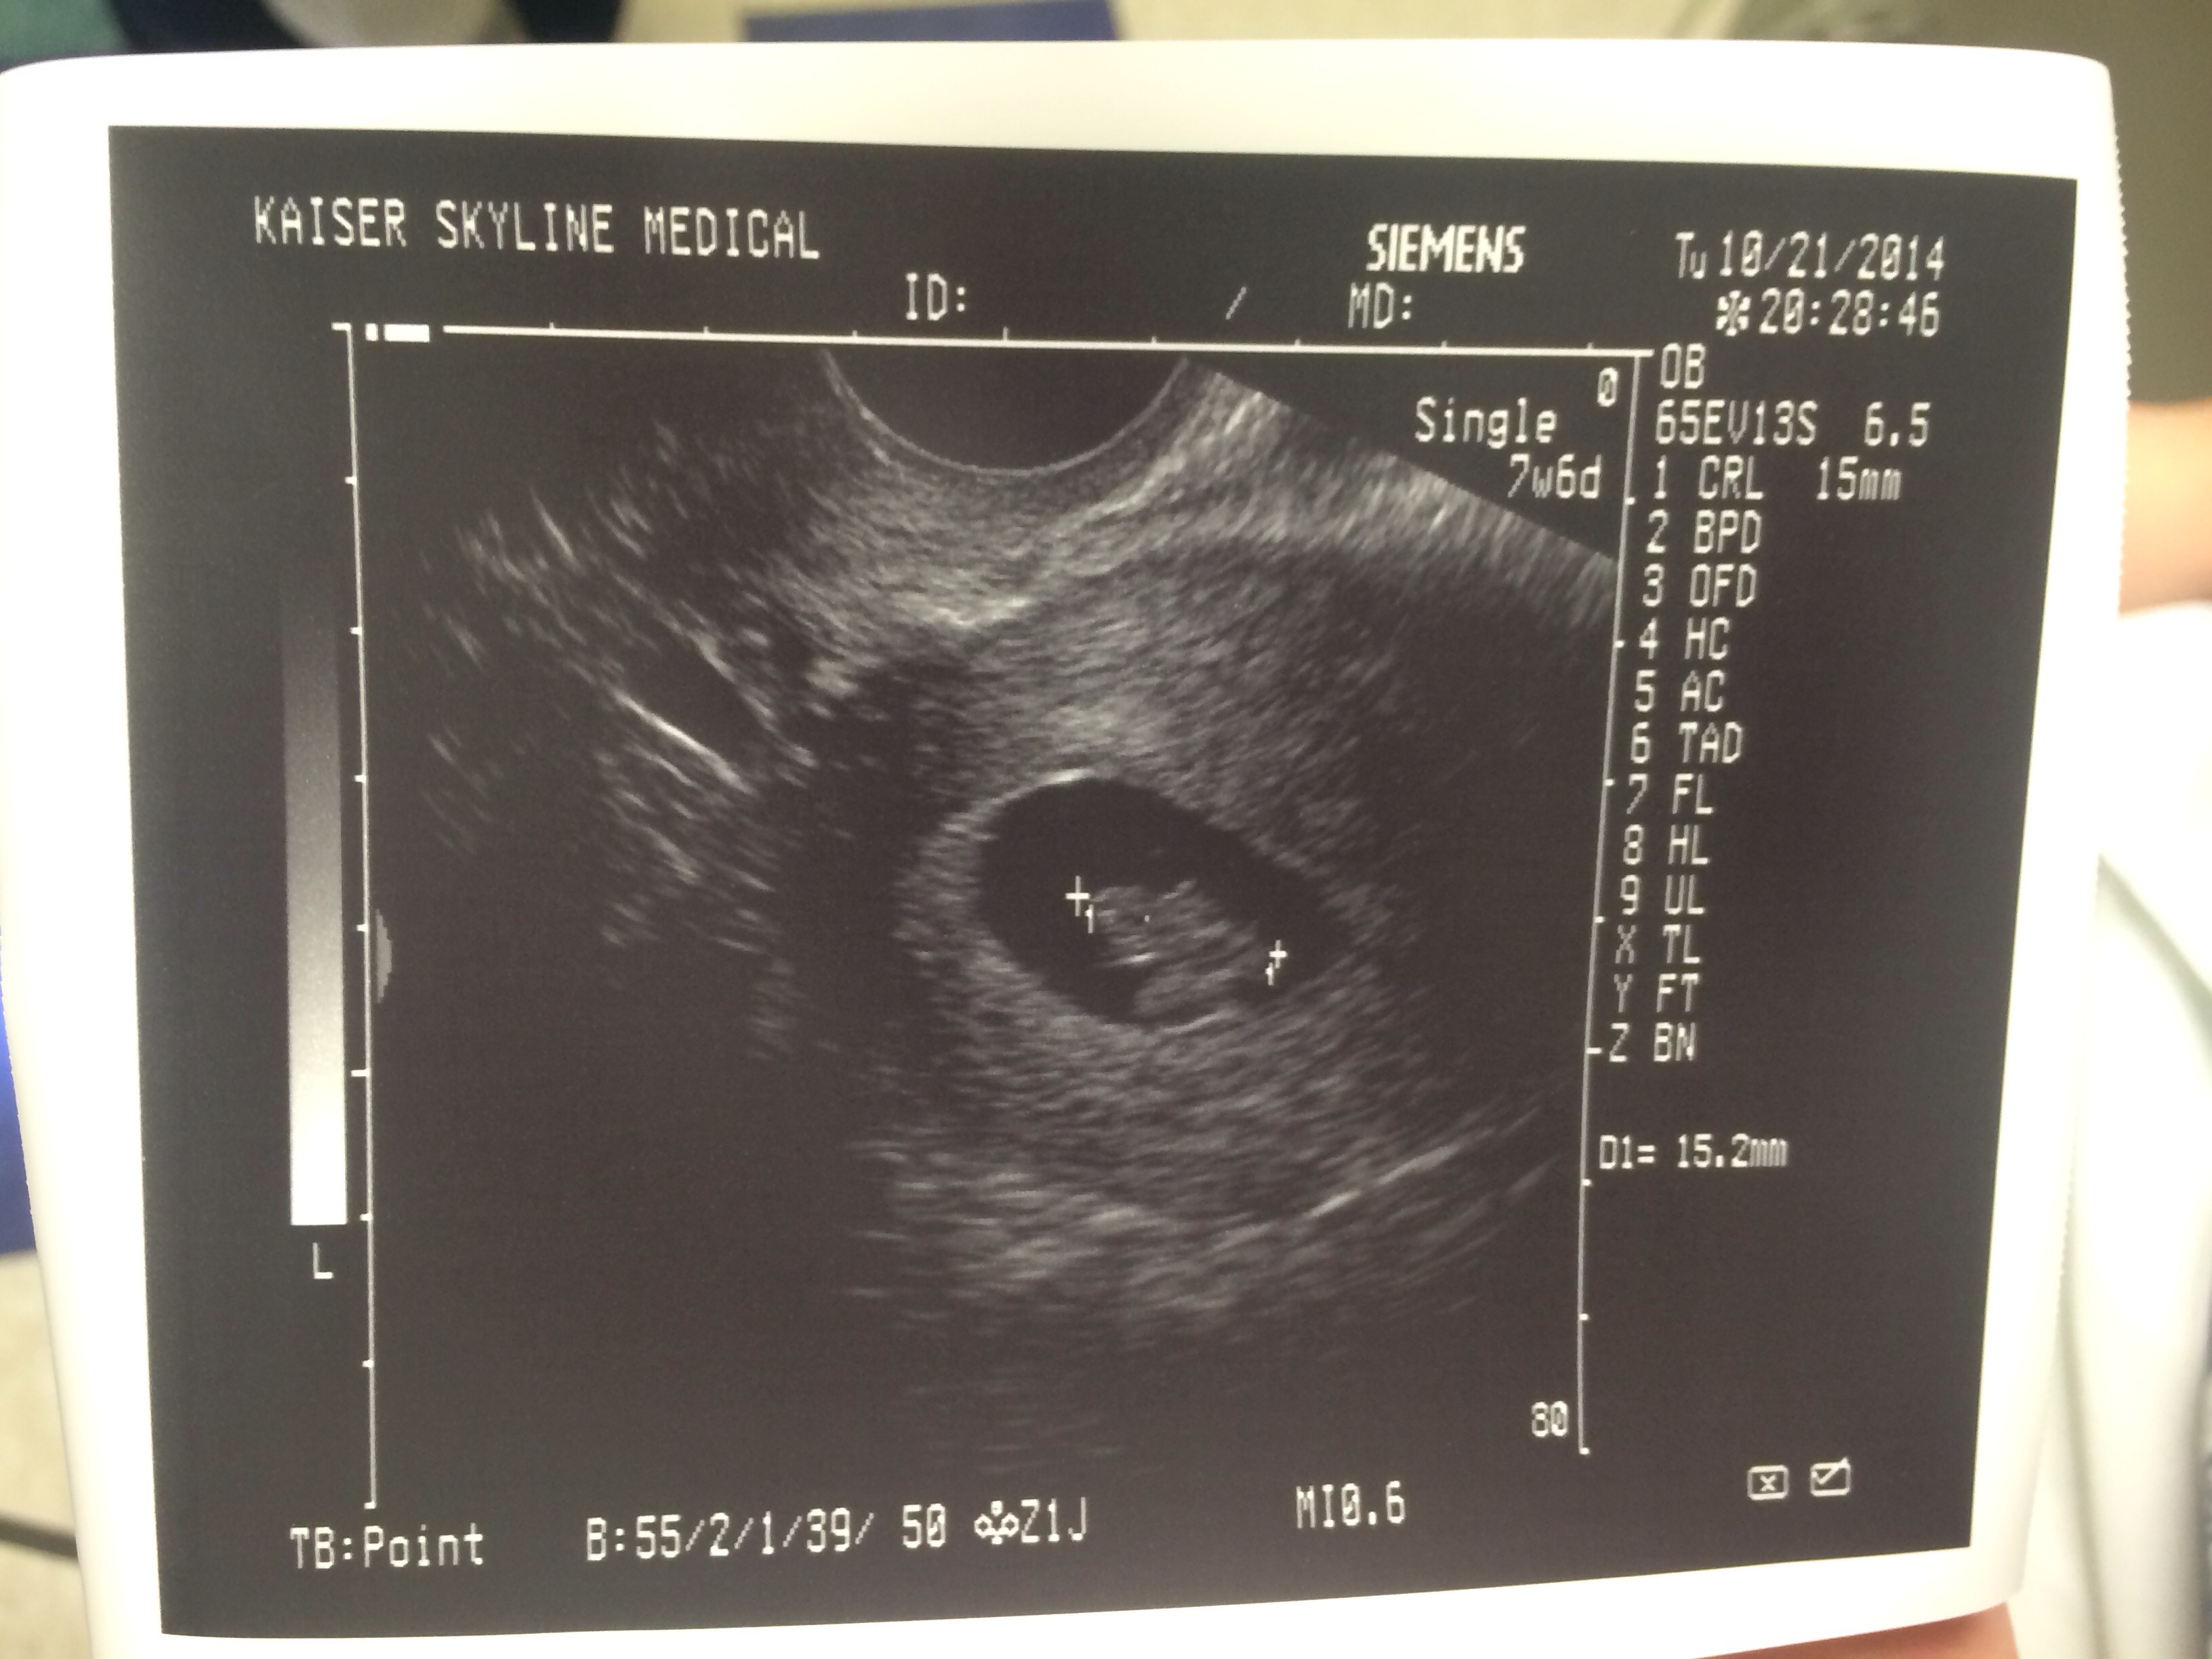

This is mine, went in 10-22 for an 8 week appointment (Kaiser Permanente insurance) turned out to be 7 weeks so I have to go back in for an "official" US on 11-3, but they still gave me a printout of my little McNugget! Seeing the heartbeat on the screen was my light bulb; I suffer from a chronic illness that makes me experience constant nausea, stomach pain and exhaustion (basically preggo without the fun prize in 9 months) so I didn't "feel" pregnant. Watching that flutter, it finally sank in.